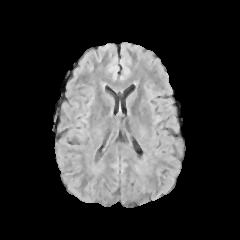

Refer to caption

(a) Healthy scan

(b) Scan presenting a tumor

(c) Highlighted lesion of the ill brain

Figure 1: Examples of MRI scans available in the dataset

Figure 1 provides examples of images labeled as healthy and ill. More specifically, 0(b) is the image of the scan of a brain containing a tumor, which is found in its lower-right part as a white area that stands out from the rest of the organ; the latter is pointed in 0(c) in the highlighted red rectangle.